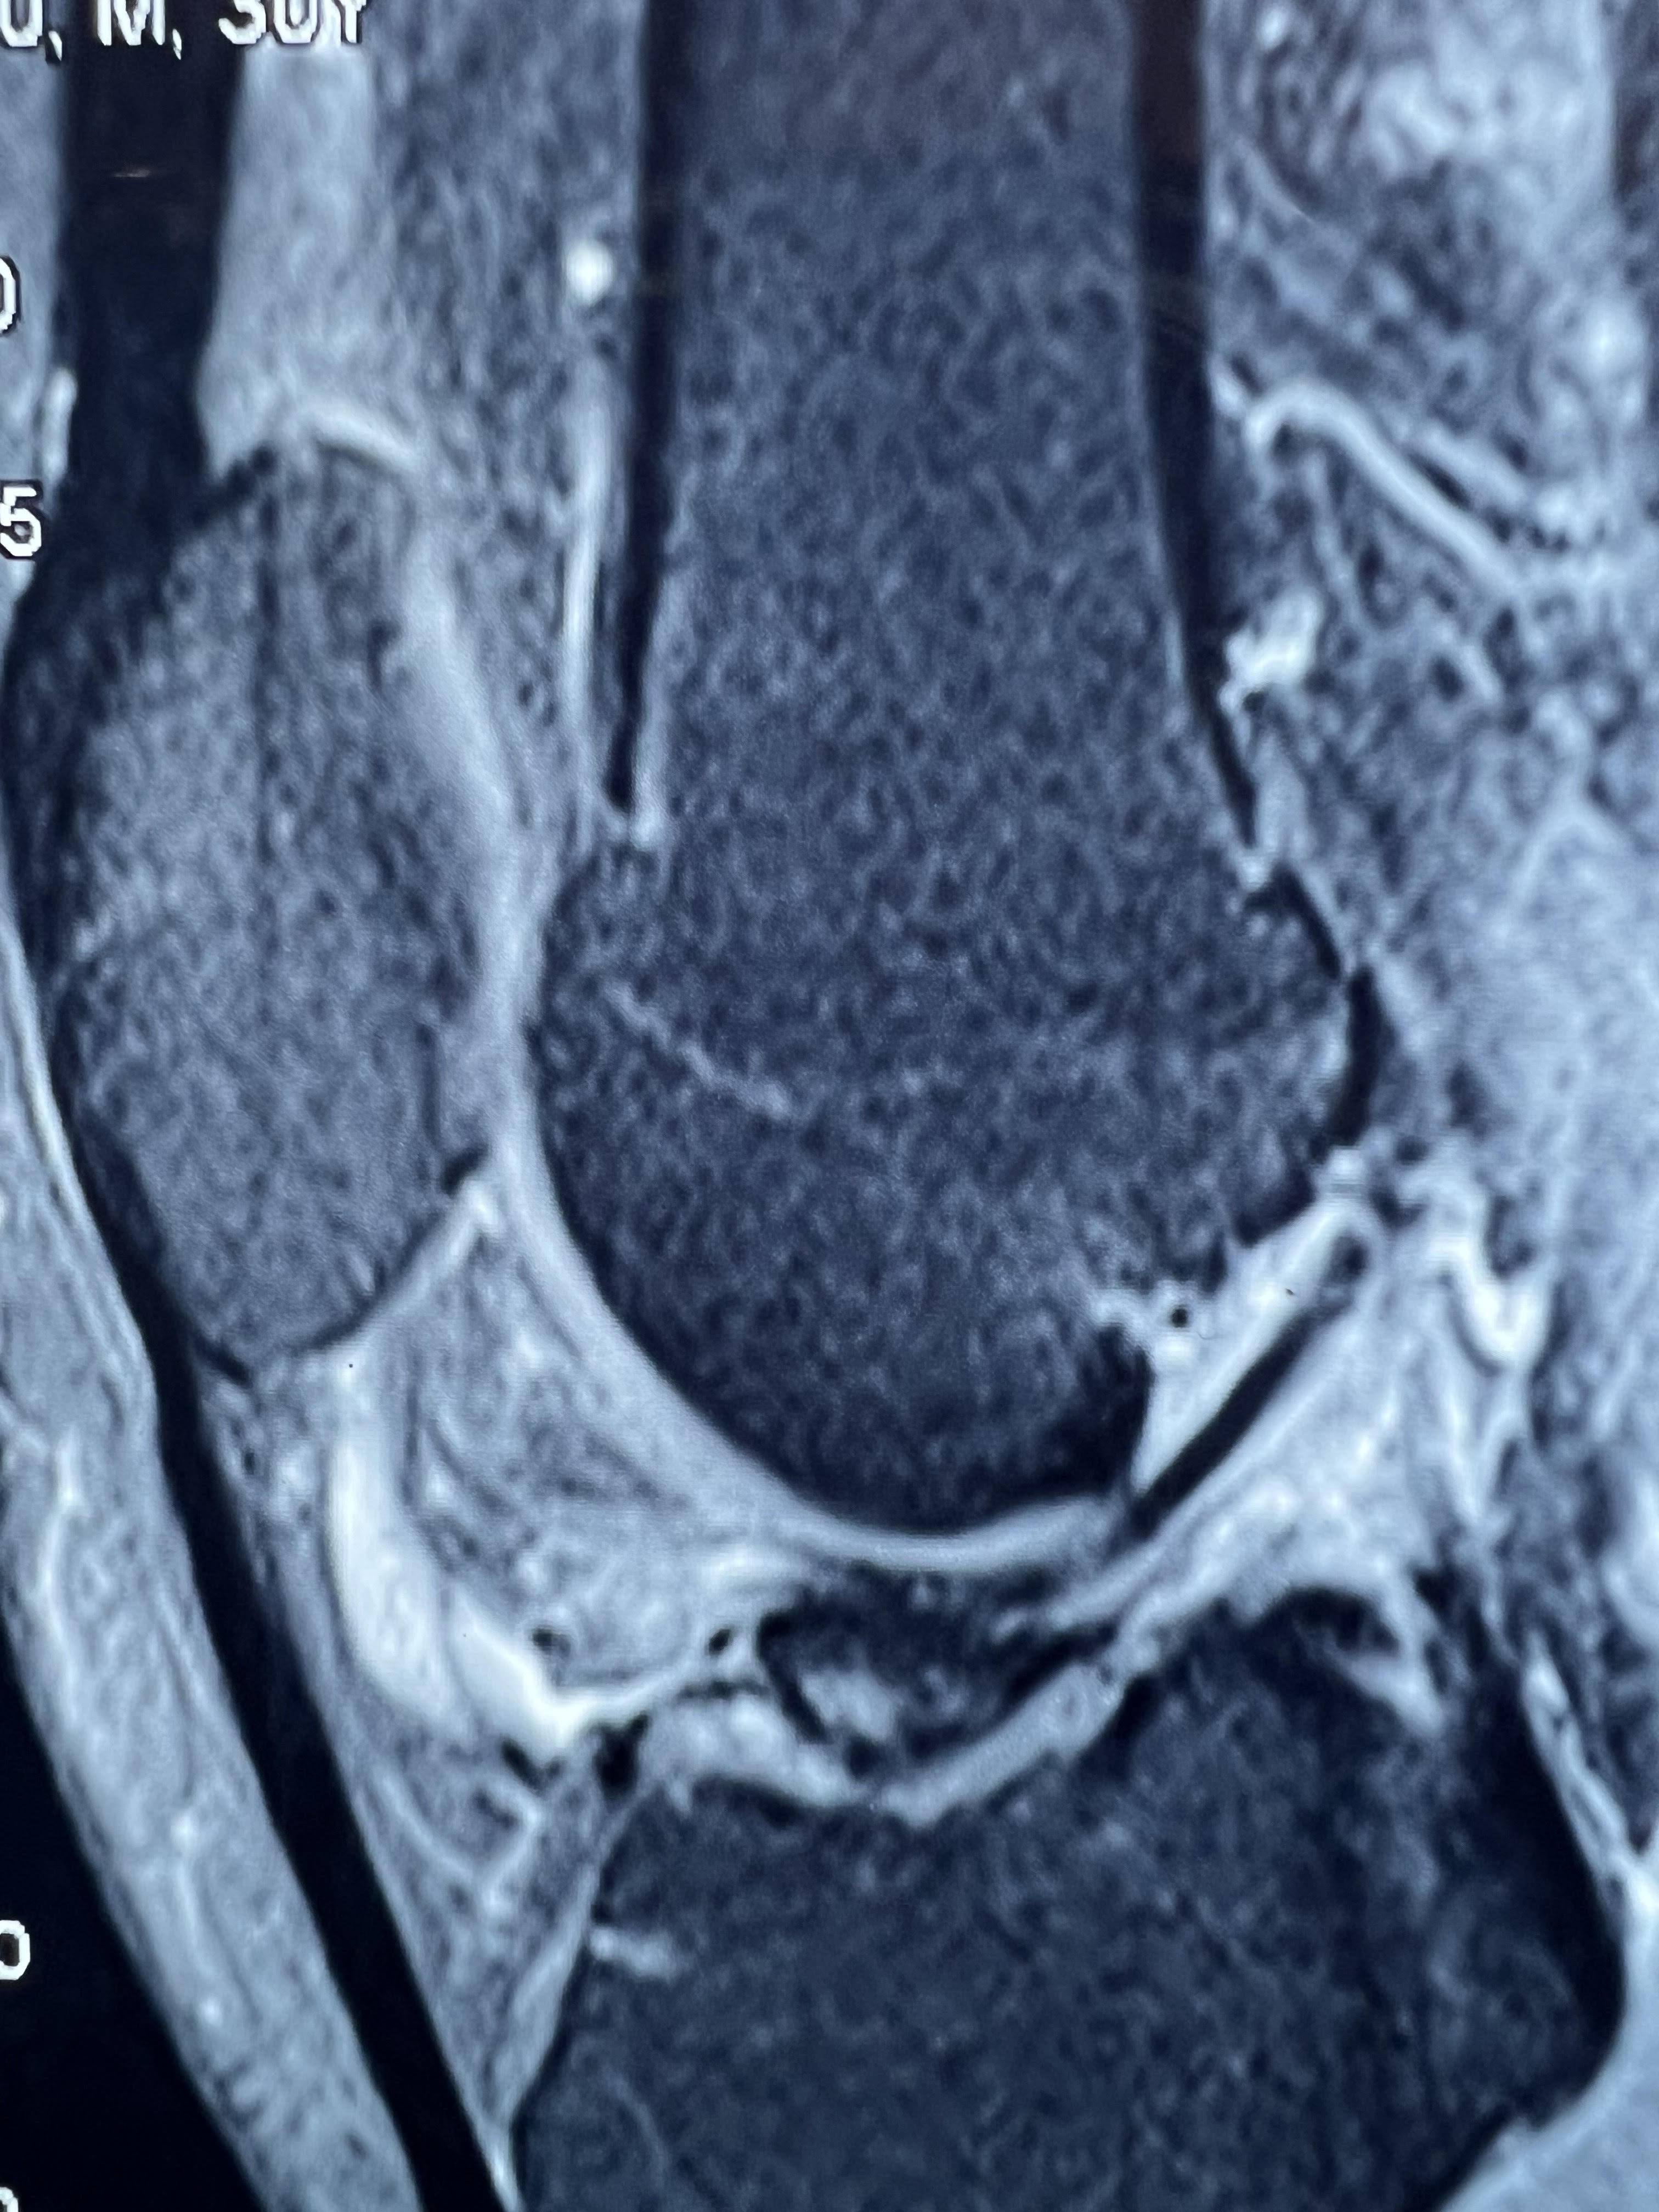

After ACL surgery, most patients can begin light jogging in about 3 months and progress to running by 6 months. However, recovery time can vary from person to person. Some patients may take longer if their thigh muscles are still weak or rehabilitation has not been adequate. If you are unable to run even after 7 months of ACL surgery, the possible reasons may include: Improper or incomplete rehabilitation exercises – Weak quadriceps and hamstring muscles can delay recovery. Loose or stretched ligament graft – This can affect knee stability and confidence while running. Failure of ACL surgery – In rare cases, the graft may not have healed properly. Associated knee problems – Meniscus or cartilage issues can also cause pain or instability. In such a situation, it is important to visit your orthopedic surgeon for a proper clinical examination. If required, your doctor may advise a 3 Tesla MRI scan to evaluate the condition of the ACL graft and bone tunnels. If the MRI shows that the graft and tunnels are normal, then focused physiotherapy and structured rehab can help you return to running. Working with a trained physiotherapist can make a big difference in regaining strength, balance, and confidence. I hope this information helps you understand the reasons and the right steps to take for a successful recovery.

You need ACL surgery if your report shows one of the following:

Complete ACL tear

high-grade ACL tear

high-grade partial tear

grade 3 ACL injury:

Most of the fibre of the ACL is torn with PCL buckling

No ACL fibre was seen